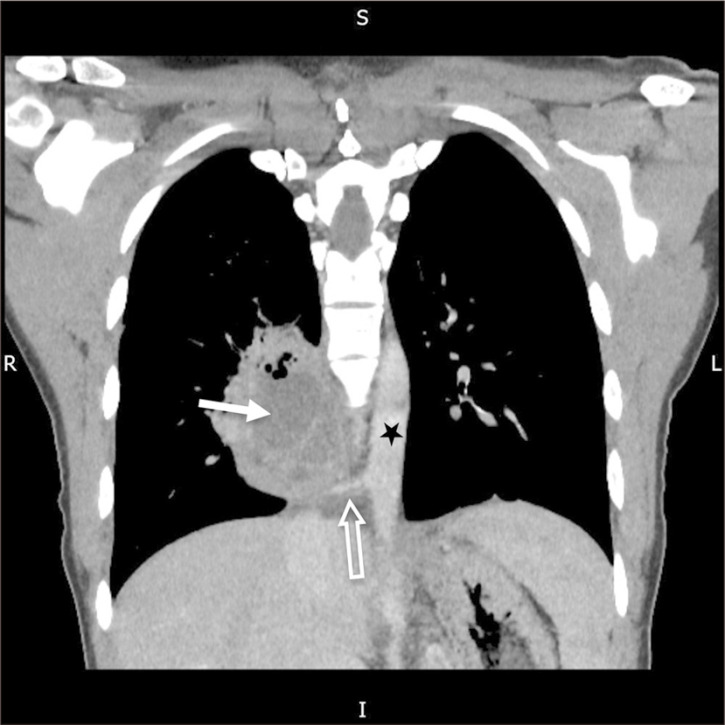

一位20岁出头的患者表现为咳嗽和炎症标志物升高。胸片显示右下区异常混浊。随后的计算机断层扫描显示右下叶脓肿,由主动脉产生的异常血管供血。这些发现与肺泡内隔离合并脓肿形成一致。患者接受抗生素治疗后出院,并计划在心胸外科医生的护理下进行选择性栓塞和肺叶切除术。一项文献综述显示,关于肺隔离的工作有限,很少有涉及类似表现的病例报告。因此,我们的病例是文献中罕见而重要的补充。

A patient in her early 20s presented with a cough and elevated inflammatory markers. A chest radiograph revealed an abnormal opacity in the right lower zone. Subsequent computed tomography showed an abscess in the right lower lobe that was fed by an anomalous vessel arising from the aorta. These findings were consistent with intralobar sequestration complicated by abscess formation. The patient was treated with antibiotics and discharged home, with plans for elective embolization and lobectomy under the care of the cardiothoracic surgeons. A literature review revealed a limited body of work on pulmonary sequestrations, with very few reported cases involving similar presentations. Thus, our case represents a rare and important addition to the literature.